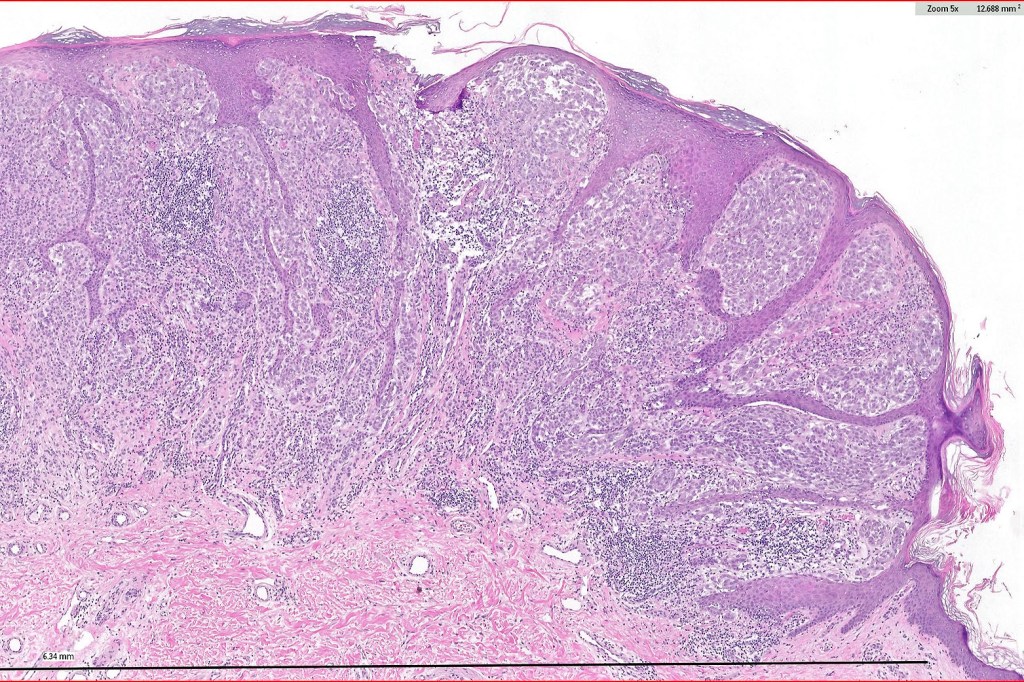

Histological features

•>5-10 mm

•Involve deep dermis or subcutis

•Asymmetrical, poorly circumscribed

•May show effacement/consumption of epidermis or ulceration

•Peripheral Pagetoid spread

•Large nodules which often show impaired maturation